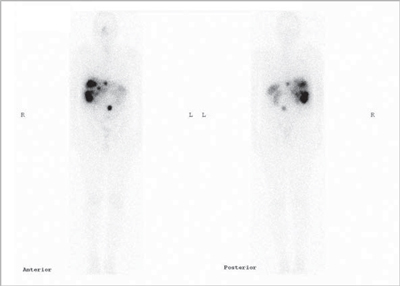

Insulinoma

Es un tumor endocrino del páncreas muy poco frecuente, se calcula su incidencia anual en 0,5-3 casos por millón de habitantes. Casi siempre está ubicado en el páncreas (1/3 en la cabeza, 1/3 en el cuerpo y 1/3 en la cola) aunque puede tener localizaciones ectópicas: duodeno, divertículo de Meckel, vía biliar, ovario y omento. Generalmente son pequeños: 40% son menores de 1 cm y 50% entre 1 y 5 cm y generalmente solitarios. Menos del 10% son múltiples, en cuyo caso debe descartarse síndrome de NEM tipo 1. Menos del 10% son malignos y 5% se presentan con metástasis, generalmente en el hígado o adenopatías regionales27 (Figura 10). Los insulinomas benignos y malignos suelen expresar receptores de somatostatina, el más frecuente es el subtipo 4 (80-90% de los casos), de moderada (10-50%) a gran intensidad (> 50% de las células tumorales) en los estudios inmunohistoquímicos. Los subtipos 1, 2 y 3 se expresan esporádicamente (40-50% de los casos) en los insulinomas benignos y malignos,generalmente en menos del 10% de las células neoplásicas. Los insulinomas benignos no expresan sstr 5 mientras que algunos malignos sí lo hacen28. Estos hallazgos están en línea con la experiencia clínica: aproximadamente el 50% de los insulinomas son positivos en la cintigrafía con pentatreotide y el tratamiento con radiopéptidos análogos de somatostatina (Lu177-DOTATATE o Y90-DOTATOC) es paliativo y sirve para ayudar al control de la hipoglicemia de estos enfermos29 (Figura 11).

Fusión SPECT/RM. Imágenes transaxiales de RM y SPECT con In111- pentatreotide.

Paciente con insulinoma metastásico. Se demuestra intensa sobreexpresión de receptores de somatostatina en metástasis hepáticas múltiples.